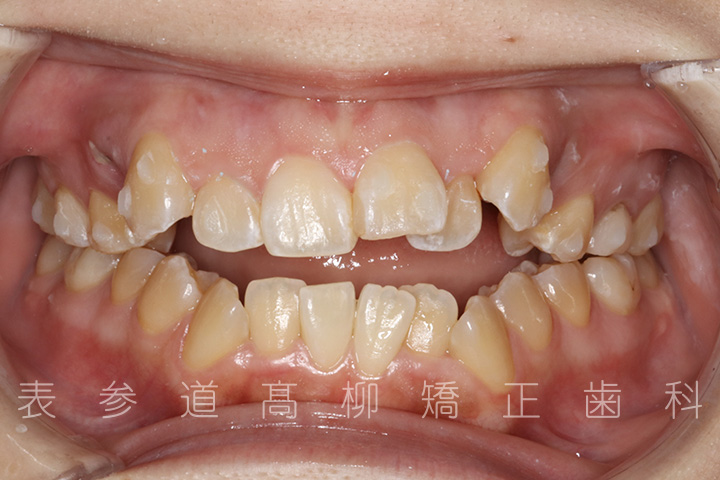

前歯のガタガタ感と開咬でお悩みの患者様の症例をご紹介いたします。

・前歯部開咬

・上下前歯部叢生(凸凹歯並び)

術前術後の比較